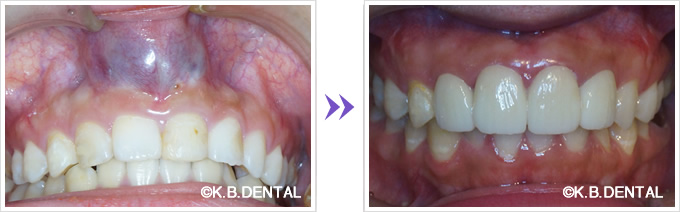

上顎外側骨隆起 症例1

咬合の応力は上顎の場合、必ずしも口蓋正中に集中するわけではありません。

歯列や歯牙の傾斜の角度により外側に分散することがあります。

その場合、上下とも外側に大きな骨隆起を生じます。

これが大きくなりすぎると食物残渣の停滞を引き起こし口腔内の不快感、口腔衛生状態の悪化につながります。

治療は外科的に除去することが第一選択肢となります。

料金

静脈内鎮静法による麻酔代込:約17万円(保険適用外)